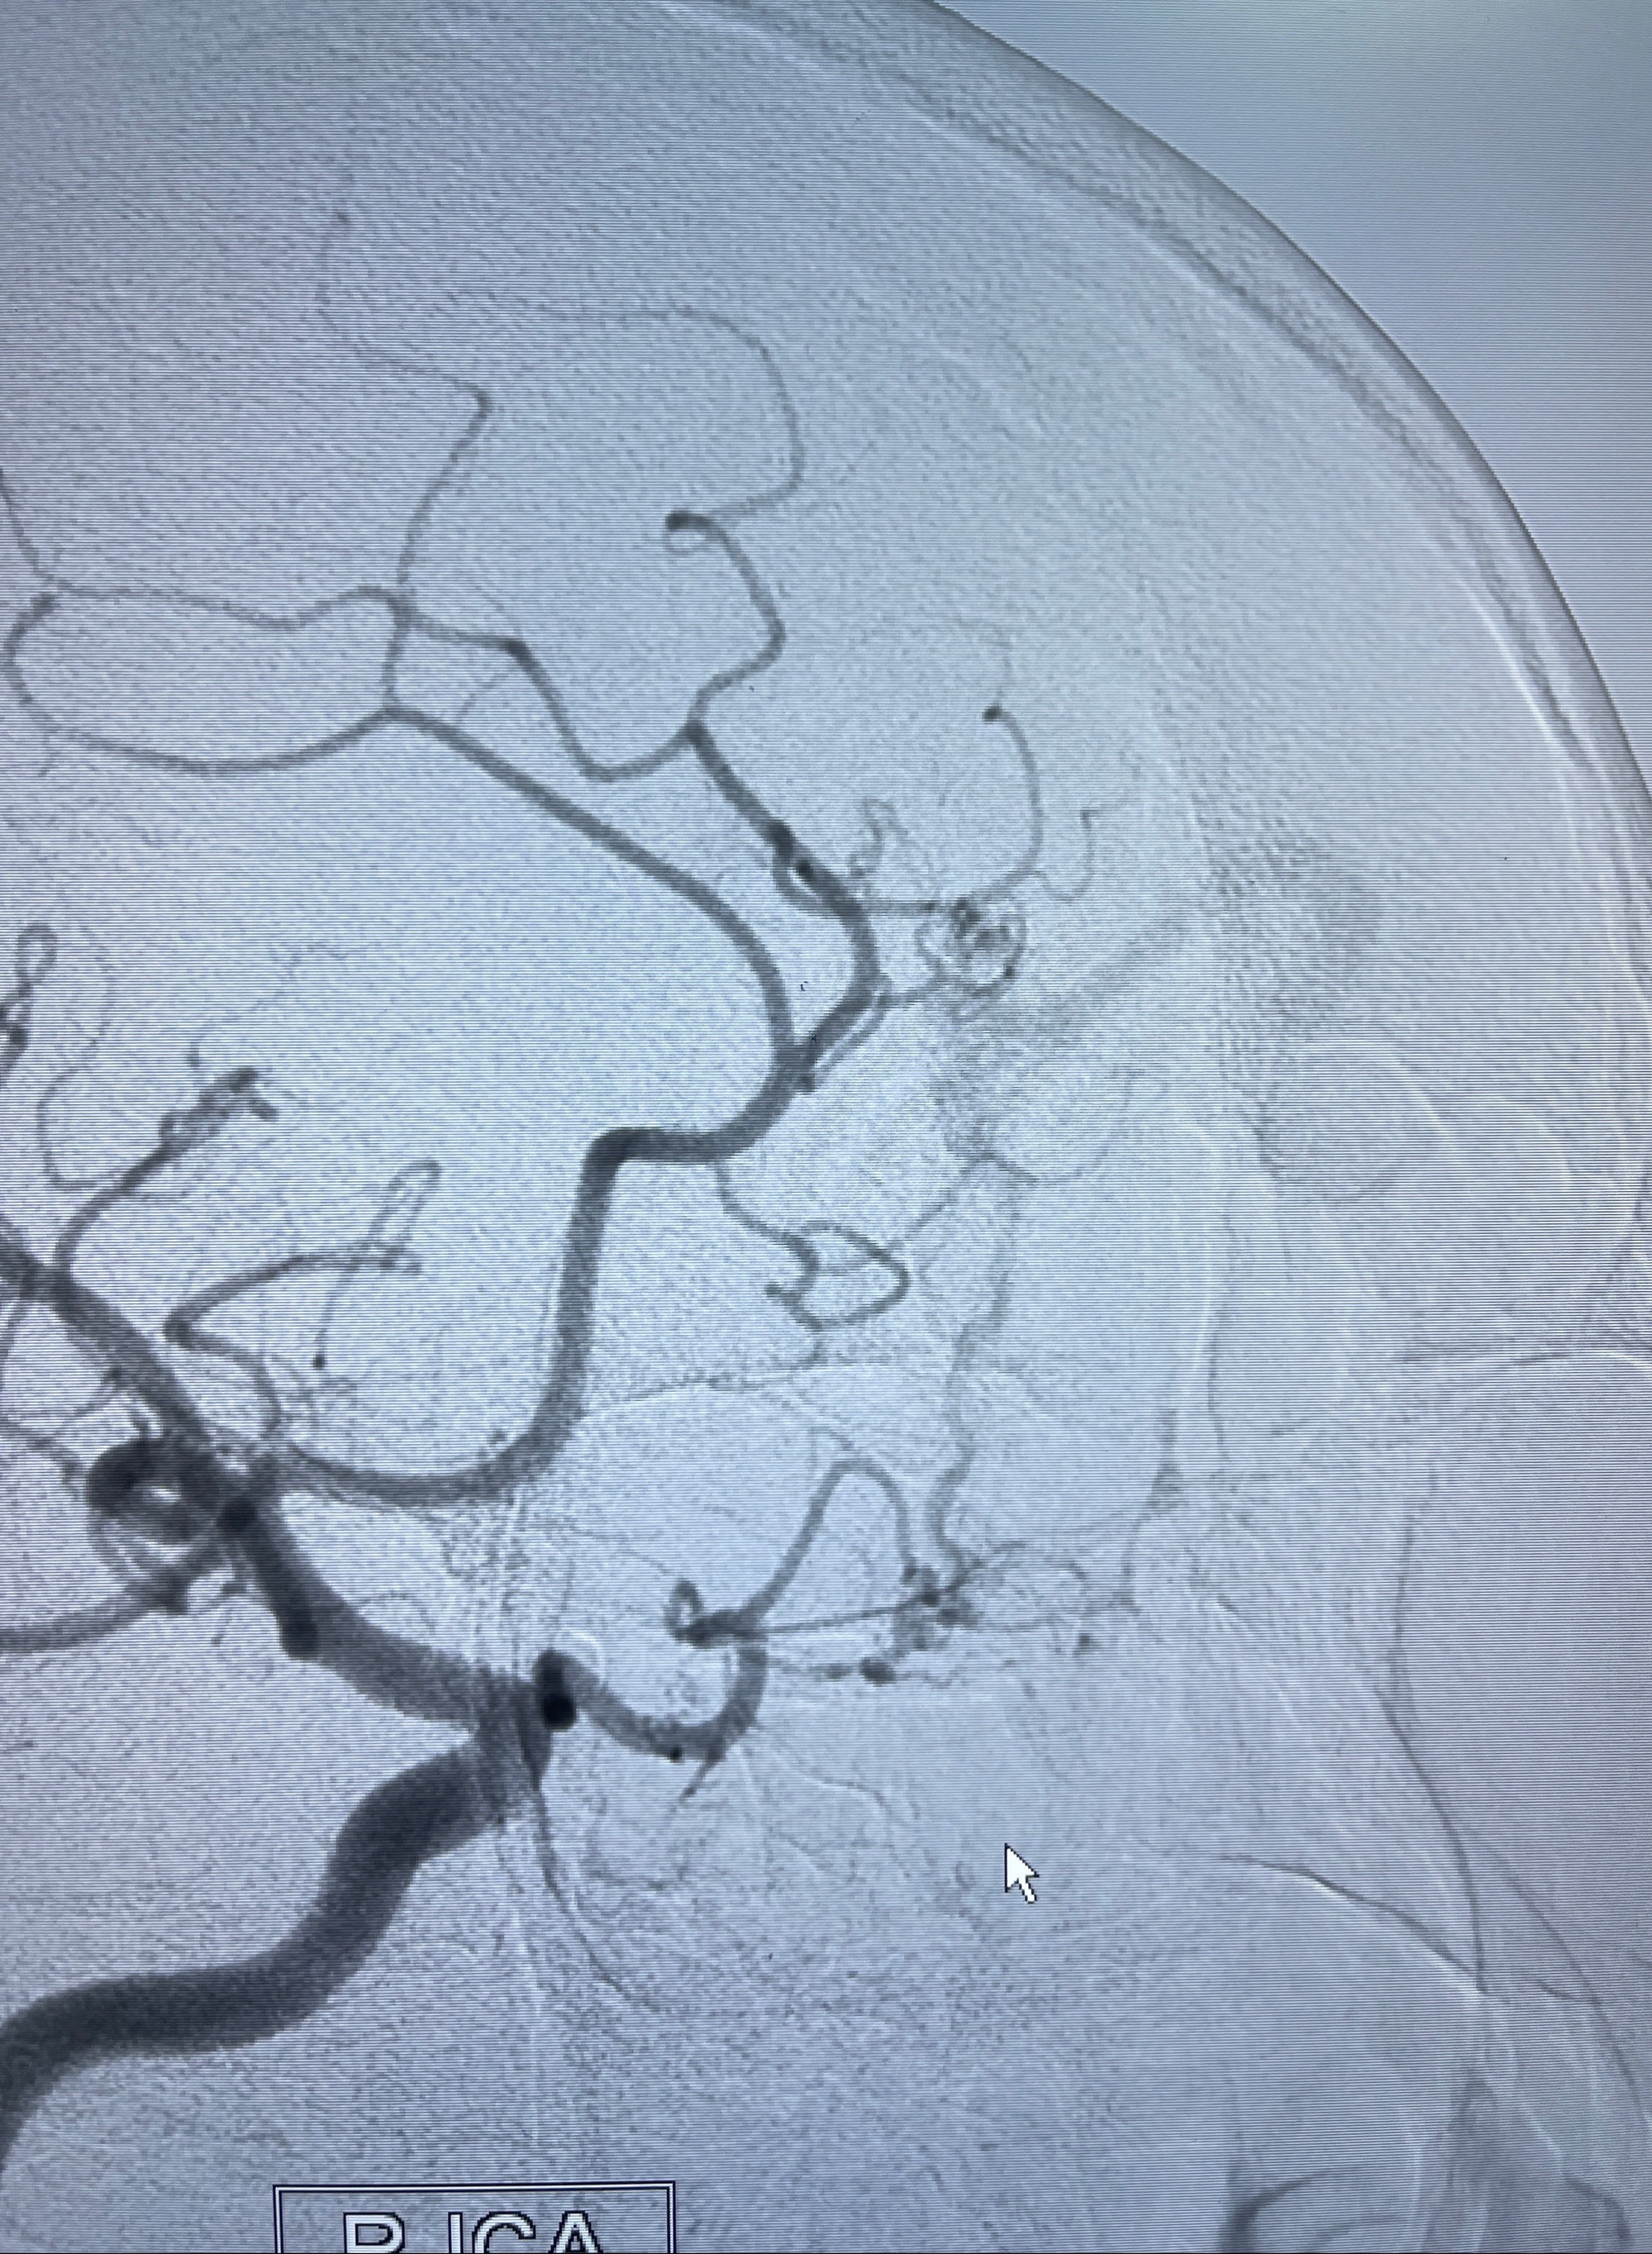

2023年8月21日]景德镇市第一人民医院脑血管造影检查,提示:主动脉弓、双侧颈总动脉、锁骨下动脉造影未见异常,左侧大脑前动脉静脉瘘。

2023-09-13全脑血管造影:前颅底硬脑膜动静脉瘘,供血动脉为双侧胼周动脉、眼动脉脑膜支,静脉向上矢状窦方向引流